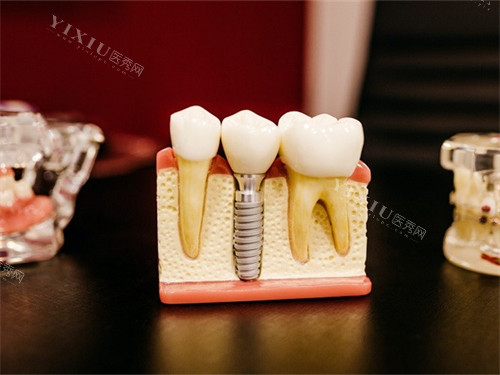

牙槽骨质量下降:

60岁后,人体钙质流失加速,牙槽骨易出现骨质疏松或吸收,导致种植体稳定性不足,增加种植失败风险。

部分患者因长期缺牙,牙槽骨宽度和高度不足,需额外进行植骨手术,延长治疗周期并增加费用。